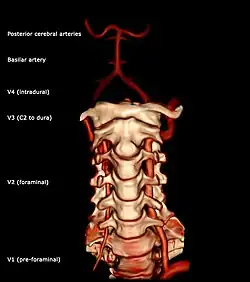

Segments of vertebral artery anterior projection

The vertebral artery may be divided into four parts:

• The first (preforaminal) part runs upward and backward between the anterior scalene and the longus colli muscles. In front of it are the internal jugular and vertebral veins, and is crossed by the inferior thyroid artery; the left vertebral is also crossed by the thoracic duct. Behind it are the transverse process of the seventh cervical vertebra, the sympathetic trunk and its inferior cervical ganglion

• The second (foraminal) part runs upward through the transverse foramina of the C6 to C2 vertebrae, and is surrounded by branches from the inferior cervical sympathetic ganglion and by a plexus of veins which unite to form the vertebral vein at the lower part of the neck. It is situated in front of the trunks of the cervical nerves, and pursues an almost vertical course as far as the transverse process of the axis.

• The third (extradural or atlantic) part issues from the C2 foramen transversarium on the medial side of the Rectus capitis lateralis. It is further subdivided into the vertical part V3v passing vertically upwards, crossing the C2 root and entering the foramen transversarium of C1, and the horizontal part V3h, curving medially and posteriorly behind the superior articular process of the atlas, the anterior ramus of the first cervical nerve being on its medial side; it then lies in the groove on the upper surface of the posterior arch of the atlas, and enters the vertebral canal by passing beneath the posterior atlantoöccipital membrane. This part of the artery is covered by the Semispinalis capitis and is contained in the suboccipital triangle—a triangular space bounded by the Rectus capitis posterior major, the Obliquus superior, and the Obliquus inferior. The first cervical or suboccipital nerve lies between the artery and the posterior arch of the atlas.

• Segments of vertebral artery lateral projection

The fourth (intradural or intracranial) part pierces the dura mater and inclines medially to the front of the medulla oblongata; it is placed between the hypoglossal nerve and the anterior root of the first cervical nerve and beneath the first digitation of the ligamentum denticulatum. At the lower border of the pons, it unites with the vessel of the opposite side to form the basilar artery.